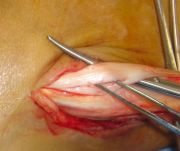

1. Ηallux valgus of the right foot in a 28-year-old female.

Treatment: Scarf osteotomy of the first metatarsal

I. Anteroposterior x-ray foot during procedure shows the scarf osteotomy with two screws II. This image shows the foot in a standing position one year down the line from the procedure. The young lady is very happy.